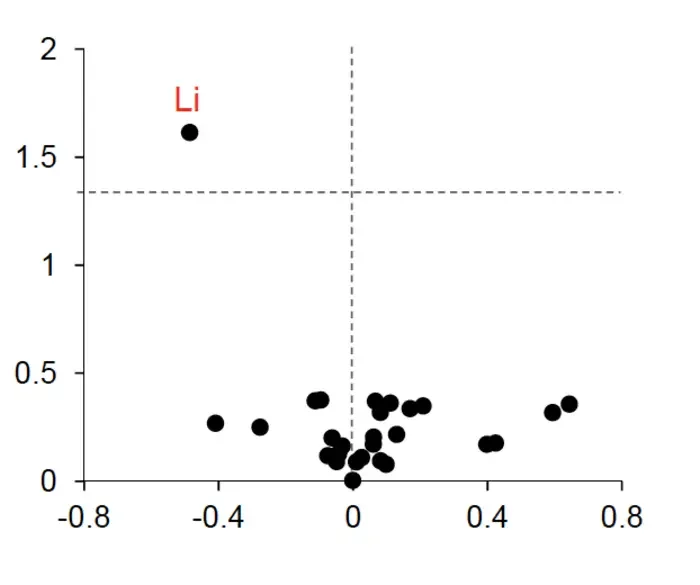

In the study, scientists used an advanced type of mass spectroscopy chemical analysis method to measure trace levels of about 30 different metals in the brain and blood samples from a range of people, including cognitively healthy people, those in an early stage of dementia, and those with advanced Alzheimer’s.

The analysis revealed that lithium was the only metal with markedly different levels across groups, which also seemed to change at the earliest stages of memory loss.

A reduced lithium level was found in some cases due to the metal’s impaired uptake and its binding to amyloid plaques, which are known to be smoking gun signs of Alzheimer’s.

Yet, researchers suspect that measuring lithium levels could help screen people for early Alzheimer’s.